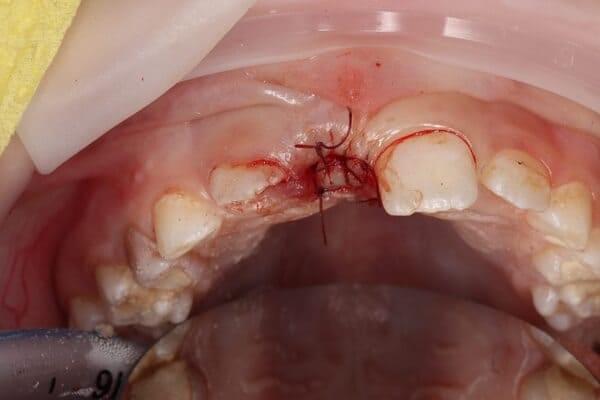

Дівчинка 7 років, перше вересня, гойдалка… Вивих постійного зуба: якщо в такій ситуації зволікати, дитина може втрати постійний зуб назавжди. Батькам порекомендували нас і пацієнти одразу приїхали. Через складність і травматичність процедур вирішено проводити лікування в анестезіологічному супроводі. Зуб поставлений на місце (репонований), проведена хірургічна обробка і ушивання рани губи. Останнє фото через рік після травми: зуб на місці і корінь продовжує розвиватись, губа повністю загоїлась